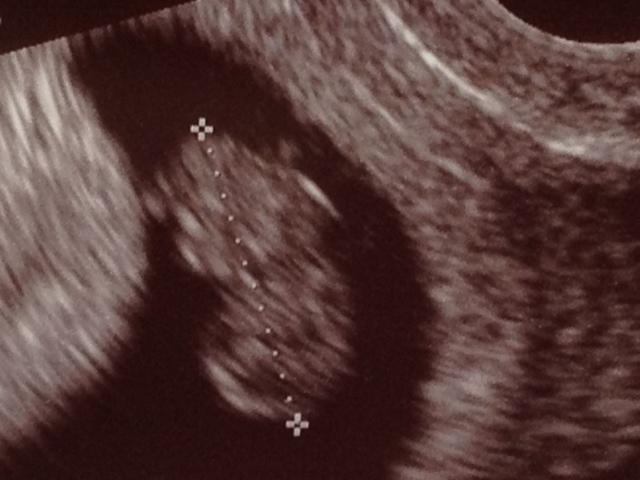

The biggest news right now is that we had our official ultrasound last Friday and everything looks GREAT. The baby is measuring right on track and had a nice fast heartbeat. It was also moving around and looked more like a gummy bear than a blob, and has almost doubled in size since the previous ultrasound, just 11 days earlier.